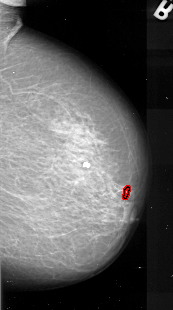

A_1081_1.LEFT_MLO

LEFT_MLO LINES 6961 PIXELS_PER_LINE 3256 BITS_PER_PIXEL 16 RESOLUTION 42 NON_OVERLAY

FILE: A_1081_1.RIGHT_MLO.OVERLAY

TOTAL_ABNORMALITIES 1

ABNORMALITY 1

LESION_TYPE CALCIFICATION TYPE PLEOMORPHIC DISTRIBUTION LINEAR

ASSESSMENT 4

SUBTLETY 4

PATHOLOGY MALIGNANT

TOTAL_OUTLINES 1

BOUNDARY